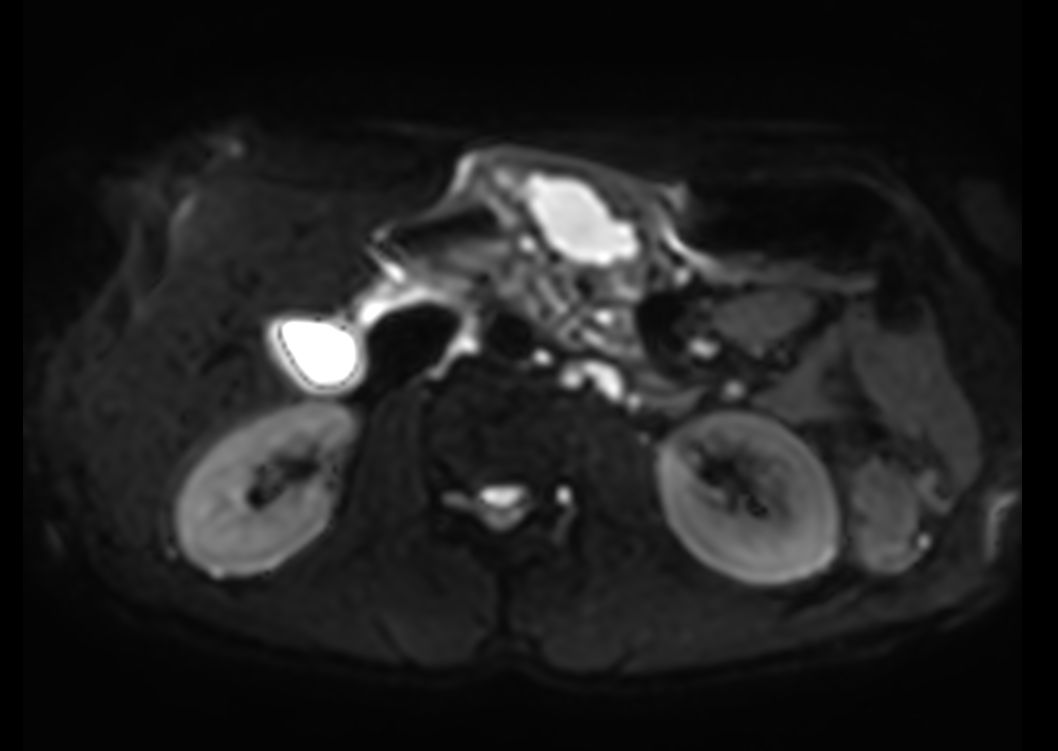

Axial DWI b10003mm slices

-

Axial DWI b503mm slices

Axial DWI b6003mm slices

Axial DWI ADC3mm slices

Axial DWI b504mm slices

Axial DWI b6004mm slices

Axial DWI ADC4mm slices